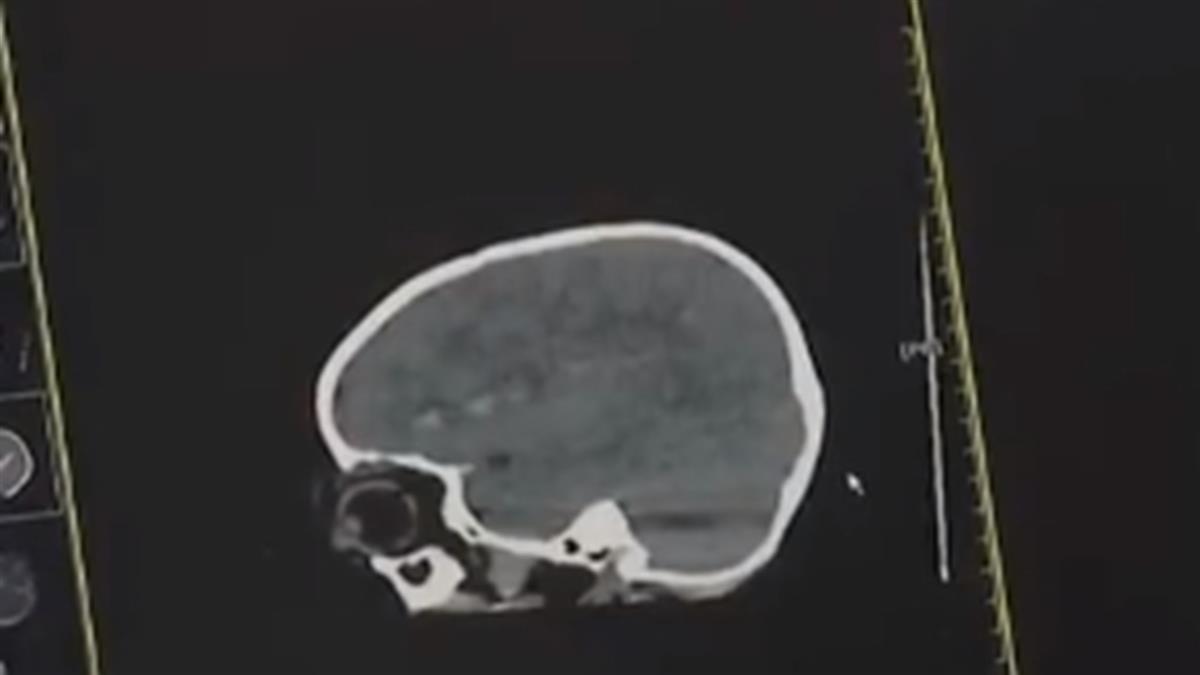

根據陸媒《福建今日熱點》報導,該名女童在緊急送醫後,醫生表示,她的左眼上方遭異物刺入,導致開放性顱腦損傷、顱內少量血腫、左眼眶上壁骨折伴隨周圍軟組織挫裂傷,所幸不鏽鋼軟軸只是從眼眶上方擦過,沒有造成眼球破裂,不過因體內出現玻璃體積血,該名女童的視力恐將受到影響。

不只這起案件,在福建還有另名女童也因這款玩具發生意外,當時乒乓球突然從軟軸掉落,女童不慎向前跌倒,不鏽鋼製的軟軸直接刺進她的左眼,緊急送醫後,發現因為異物刺入導致女童顱內出血,神經外科醫生立即開刀將軟軸拔出,在狀況穩定後,才轉院繼續治療。